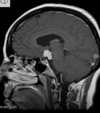

Q

A

Esclerose mesial temporal

Observe a perda de volume, que indica atrofia e causa aumento secundário do corno temporal do ventrículo lateral.

O sinal alto no hipocampo reflete a gliose.